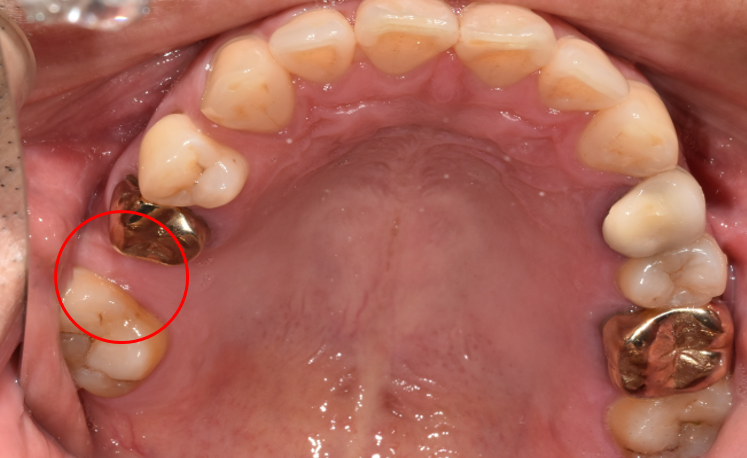

2단계는 '픽스처'로 치아 기둥을 식립합니다.

단단한 지지대 역할을 하는 픽스처는 잇몸 속 턱뼈 안에 심게 됩니다. 자연치아처럼 '단단히 고정'될 수 있도록 치아의 기둥 역할을 해줍니다.

청담역치과 2021-07-27 픽스처 심은 모습

잇몸 안에서 픽스처가 자리 잡는 데는 시간이 필요합니다.